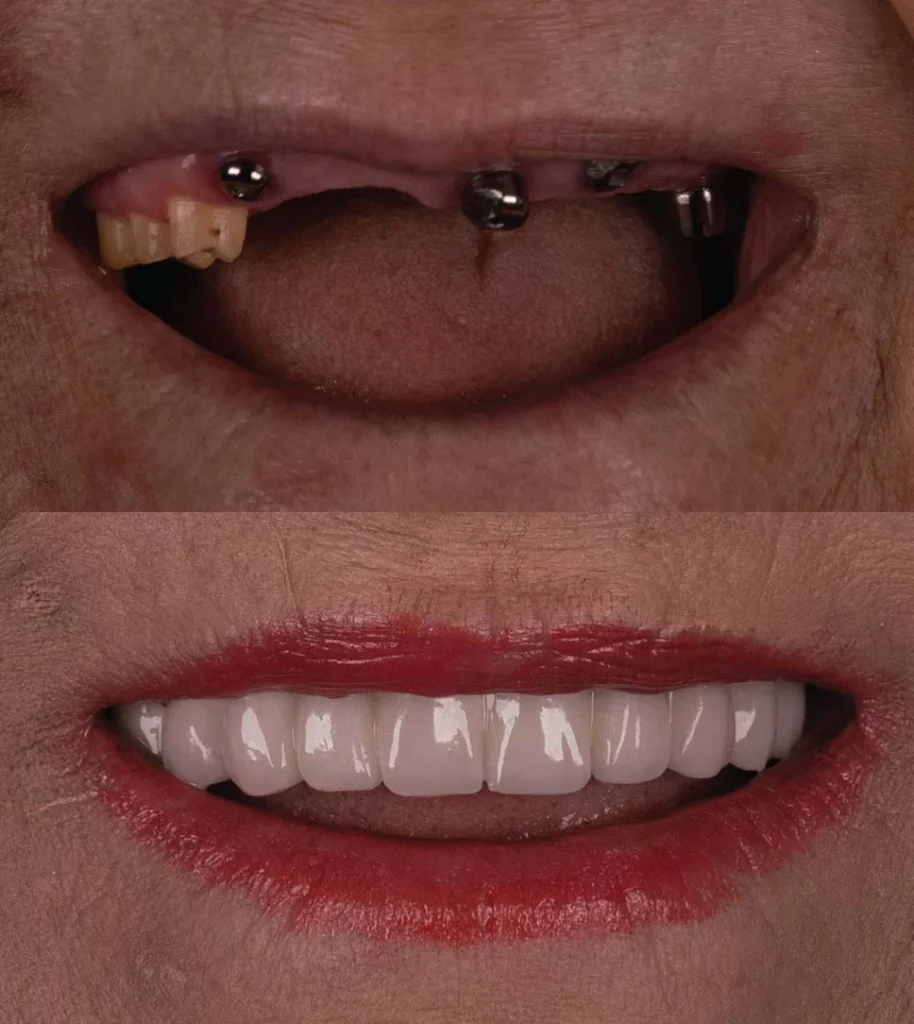

Comprehensive Full Arch Restoration with Minimal Implants

The All-on-4 implant technique revolutionizes full arch dental restoration by using just four strategically placed implants to support a complete set of fixed, non-removable teeth. This method is particularly beneficial for patients with significant tooth loss or those seeking a more cost-effective solution compared to traditional full arch implants.

Achieve a Functional Smile Instantly

Immediate loading implants allow you to receive a functional prosthesis on the same day as your implant placement. This innovative approach minimizes the number of visits and significantly reduces the overall treatment time, providing you with a complete smile in a single appointment.